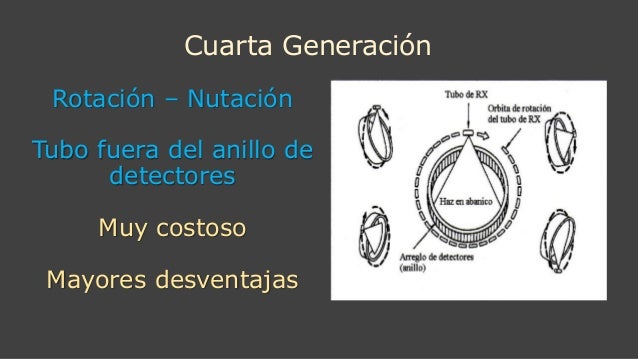

CUARTA GENERACIÓN 1976

TIPO II

ROTACIÓN NUTACIÓN

Anillo de detectores pero el tubo de RX gira por fuera

Adquisición 1 seg.

1.000 X 1.000 pixeles